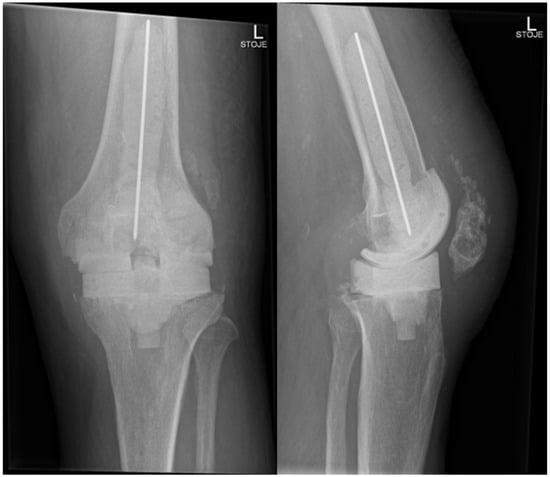

In November 2024, four and a half weeks later, the second stage was performed, involving the removal of the spacer and reimplantation of the revision prosthesis. The reimplantation procedure was a complex and surgically demanding procedure. A significant bone defect, in combination with a degenerative cyst in the lateral femoral condyle, required careful management during the reimplantation procedure. The cyst added complexity to the structural integrity of the femoral condyle, demanding attention to ensure proper fixation of the new prosthesis. Additionally, wound closure proved difficult, since it was impacted by scar tissue resulting from the previous two surgeries. Moreover, the patient had an attenuated quadriceps tendon, which added to the challenges of achieving stable joint function post-revision. The weakened tendon posed a risk for compromised rehabilitation and further functional limitations. Tissue samples, including synovial tissue and a portion of patellar bone with residual non-resorbable suture material and spacer, were once again obtained for microbiological analysis. The spacer was sonicated, and the sonication fluid was cultured. Preoperatively, the patient received 70 mg intravenous caspofungin, piperacillin/tazobactam at 4.5 g every 8 h, and 1–1.5 g of vancomycin every 12 h (depending on serum levels) until the microbiological results of the intraoperative samples were available. Tissue samples remained sterile, and after two weeks, the patient was discharged home on oral fluconazole therapy (400 mg/day) for the next 6 months. A prolonged suppressive antifungal therapy is planned thereafter (200 mg daily for the next 6–12 months). Upon discharge, inflammatory parameters were in decline (CRP 13 mg/dL), and the surgical wound was adequately healed. At the last follow-up check-up 11 months after the surgery in October 2025, the patient’s knee was painless, without effusion, and the surgical wound healed. The knee mobility was from 0 to 100 degrees, and greater flexion is not expected due to the quadriceps scar. The patient is pain-free and can handle all daily loads. The Knee injury and Osteoarthritis Outcome Score (KOOS) is 84. Inflammatory markers remained negative, indicating no signs of infection or ongoing inflammation. The patient experienced no side effects from antifungal therapy. He is still on fluconazole 200 mg orally, but the suppressive therapy will be stopped in 1 month (12 months after surgery). Further careful clinical monitoring is planned. This clinical progression suggests a favorable post-revision outcome, with the patient tolerating the suppressive antifungal treatment well. The patient is satisfied with the treatment result. In Figure 5, radiography after the reimplantation of the revision endoprosthesis is presented.

Figure 5. Radiography of the left knee—anteroposterior and lateral views after reimplantation of revision knee endoprosthesis.